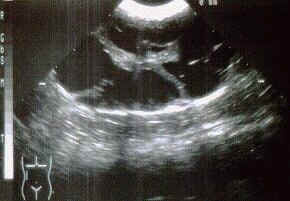

Normale Katzenniere